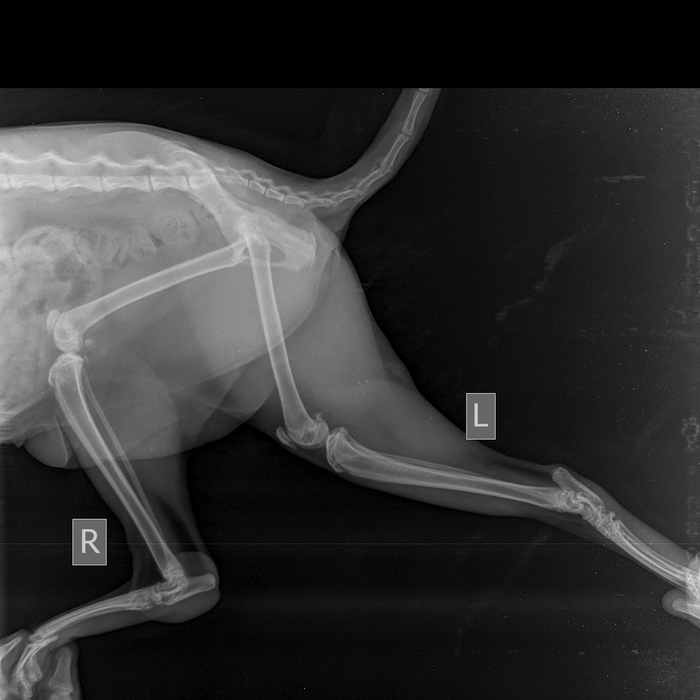

2 августа эта красота решила отметить праздник. Отодрала сетку с балконного окна и сиганула с 5 этажа без парашюта (скорее всего голуби радразнили). Дома никого не было. Судя по всему приземлилась на газон, доковыляла до околопод'ездной лавочки и дождалась меня. -1 кошачья жизнь, контузия правого легкого, ушиб двух правых лап, обошлось без переломов.